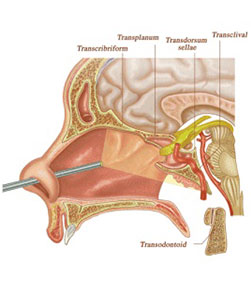

- Brain tumors - More than 1800 including pituitary, posterior fossa, intraventricular lesions, suprasellar lesions and intrinsic brain tumors

- Endoscopic brain surgeries - More than 300 endoscopic third ventriculostomies, 30 ventricular tumors.